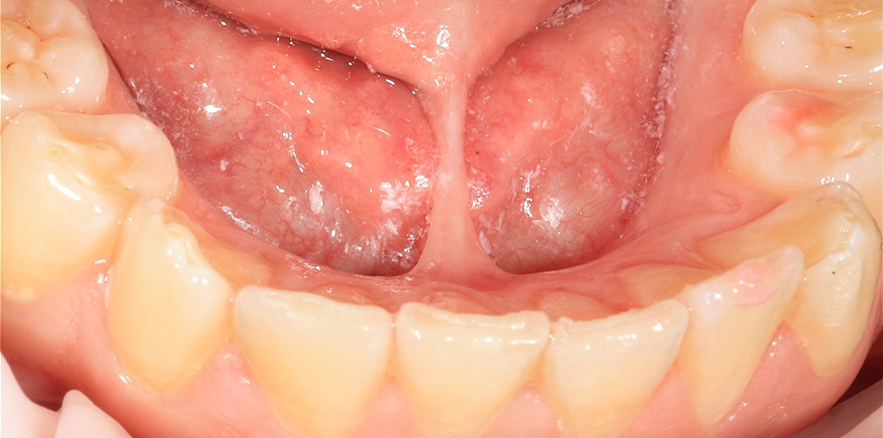

Красивая и аккуратная работа, по пластике уздечки языка. Короткая уздечка сильно ограничивает положение и движение языка. Процедура проведена диодным хирургическим лазером, быстро и безболезненно.

После лечения